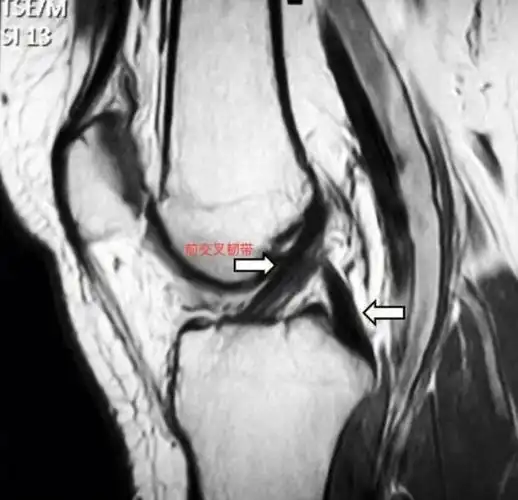

前交叉韧带|五张图复习一下 前交叉韧带(acl)起自股骨髁间窝的外侧面